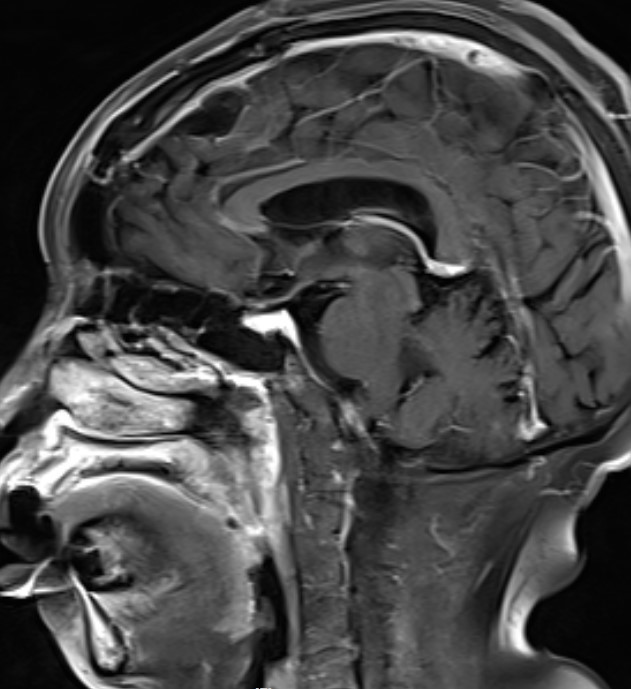

患者女性,62岁,因头晕一月在外院检查头部MR发现左额镰窦旁肿瘤来我院

完善术前检查在全麻下行左额开颅肿瘤切除术

手术精要:1 肿瘤基底在大脑镰,切口过中线,骨窗显露矢状窦边缘;2  翻开硬膜及切除肿瘤时注意肿瘤周围尤其是肿瘤表面的引流静脉的保护;3 肿瘤切除策略锐性分离,分块切除,优先阻断肿瘤基底血供